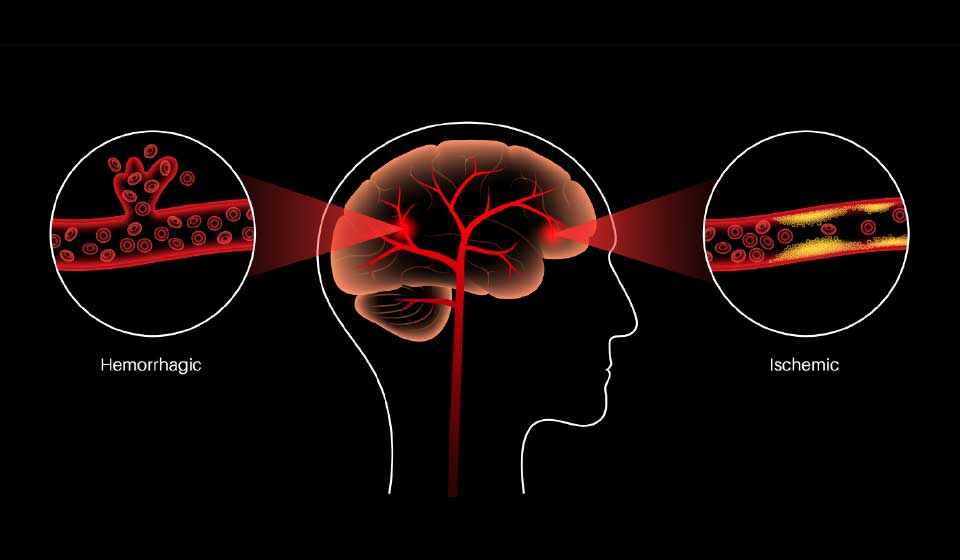

โรคหลอดเลือดสมองมีทั้งหมด 3 ชนิด

- หลอดเลือดสมองตีบ เกิดจากหลอดเลือดแดงแข็งและตีบลงเรื่อย ๆ

- หลอดเลือดสมองอุดตัน เกิดจากลิ่มเลือดอุดตัน มักพบในผู้ที่มีภาวะหัวใจเต้นผิดจังหวะหรือหลอดเลือดหัวใจตีบ

- หลอดเลือดสมองแตก อันตรายที่สุด เกิดจากหลอดเลือดที่เปราะบางและแตกได้ง่าย ทำให้เสียชีวิตได้อย่างรวดเร็ว